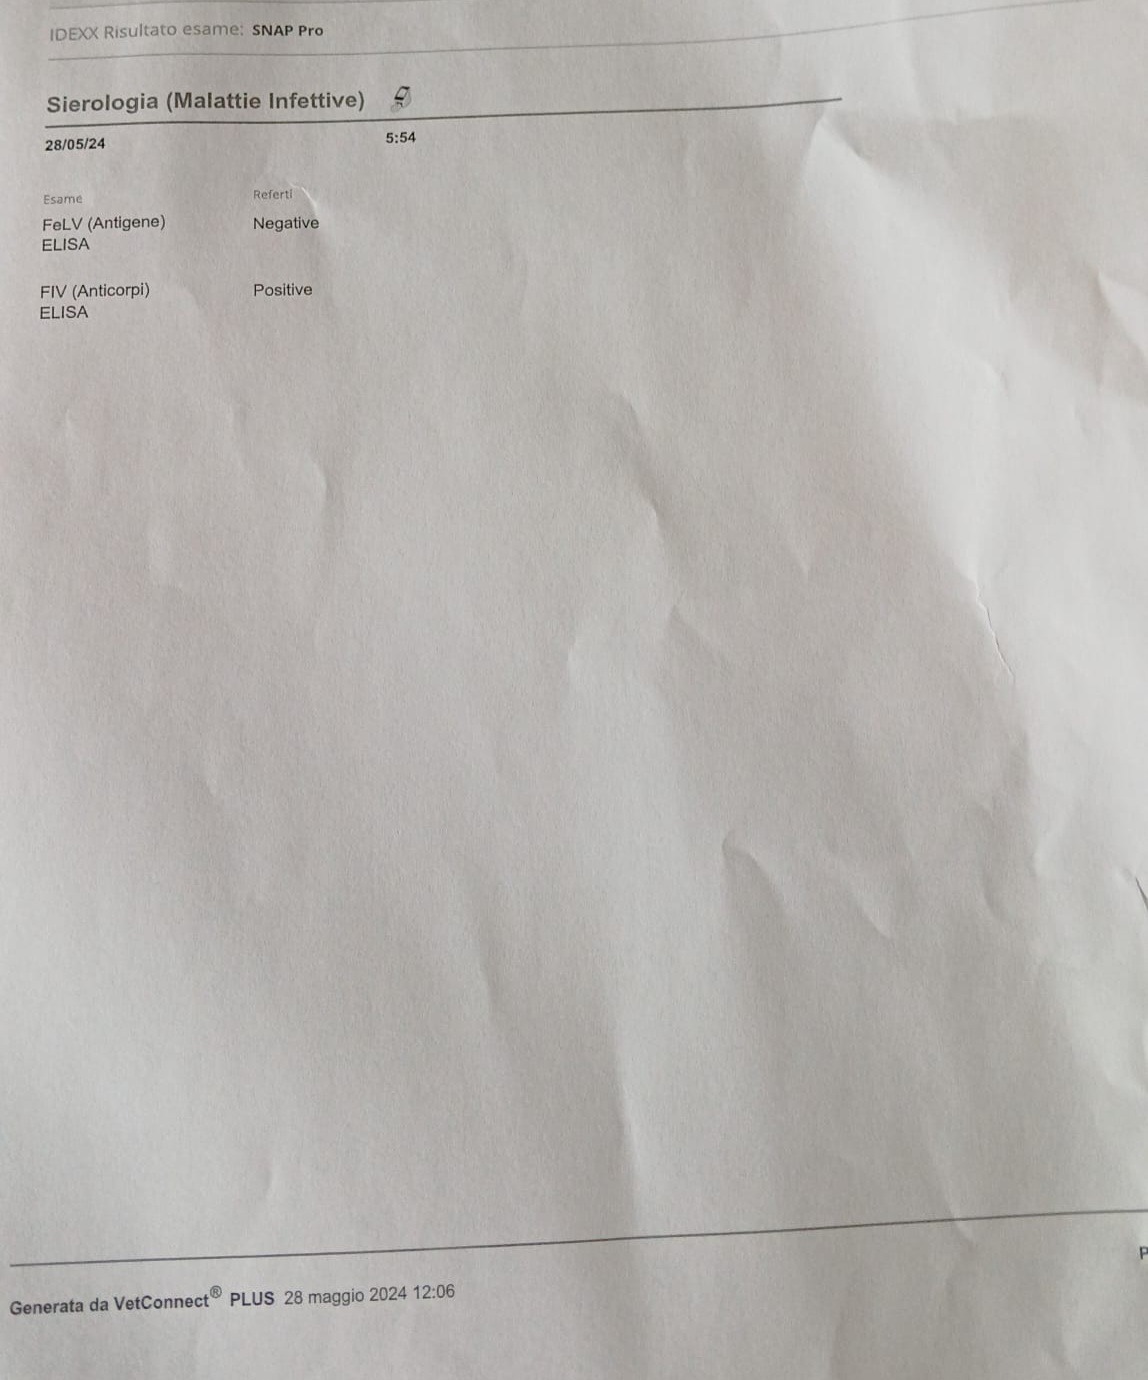

Sono stati fatti un sacco di esami ed eco, tra cui è risultata Positiva alla fiv, è stata prontamente sterilizzata dalla sua tata Ilde, ma purtroppo le disgrazie non finiscono qui, Titty ha un'ernia che va operata con urgenza, il costo dell'intervento più esami e degenza è quello che vedete nel preventivo, abbiamo bisogno di una mano per le spese